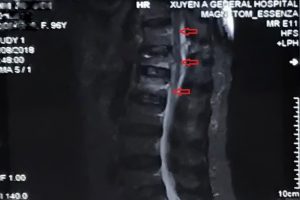

Bệnh viện Đa khoa Xuyên Á – Vĩnh Long (BVXA – VL) đã tiến hành phẫu thuật tạo hình thân sống bằng phương pháp bơm cement sinh học điều trị thành công cho hai bệnh nhân lớn tuổi bị xẹp đốt sống do loãng xương.